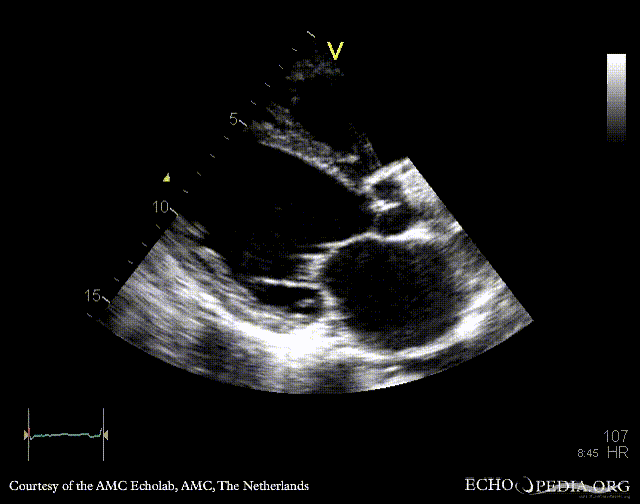

A5CH: vegetation on aortic valve A5CH with Color Doppler: severe aortic regurgitation